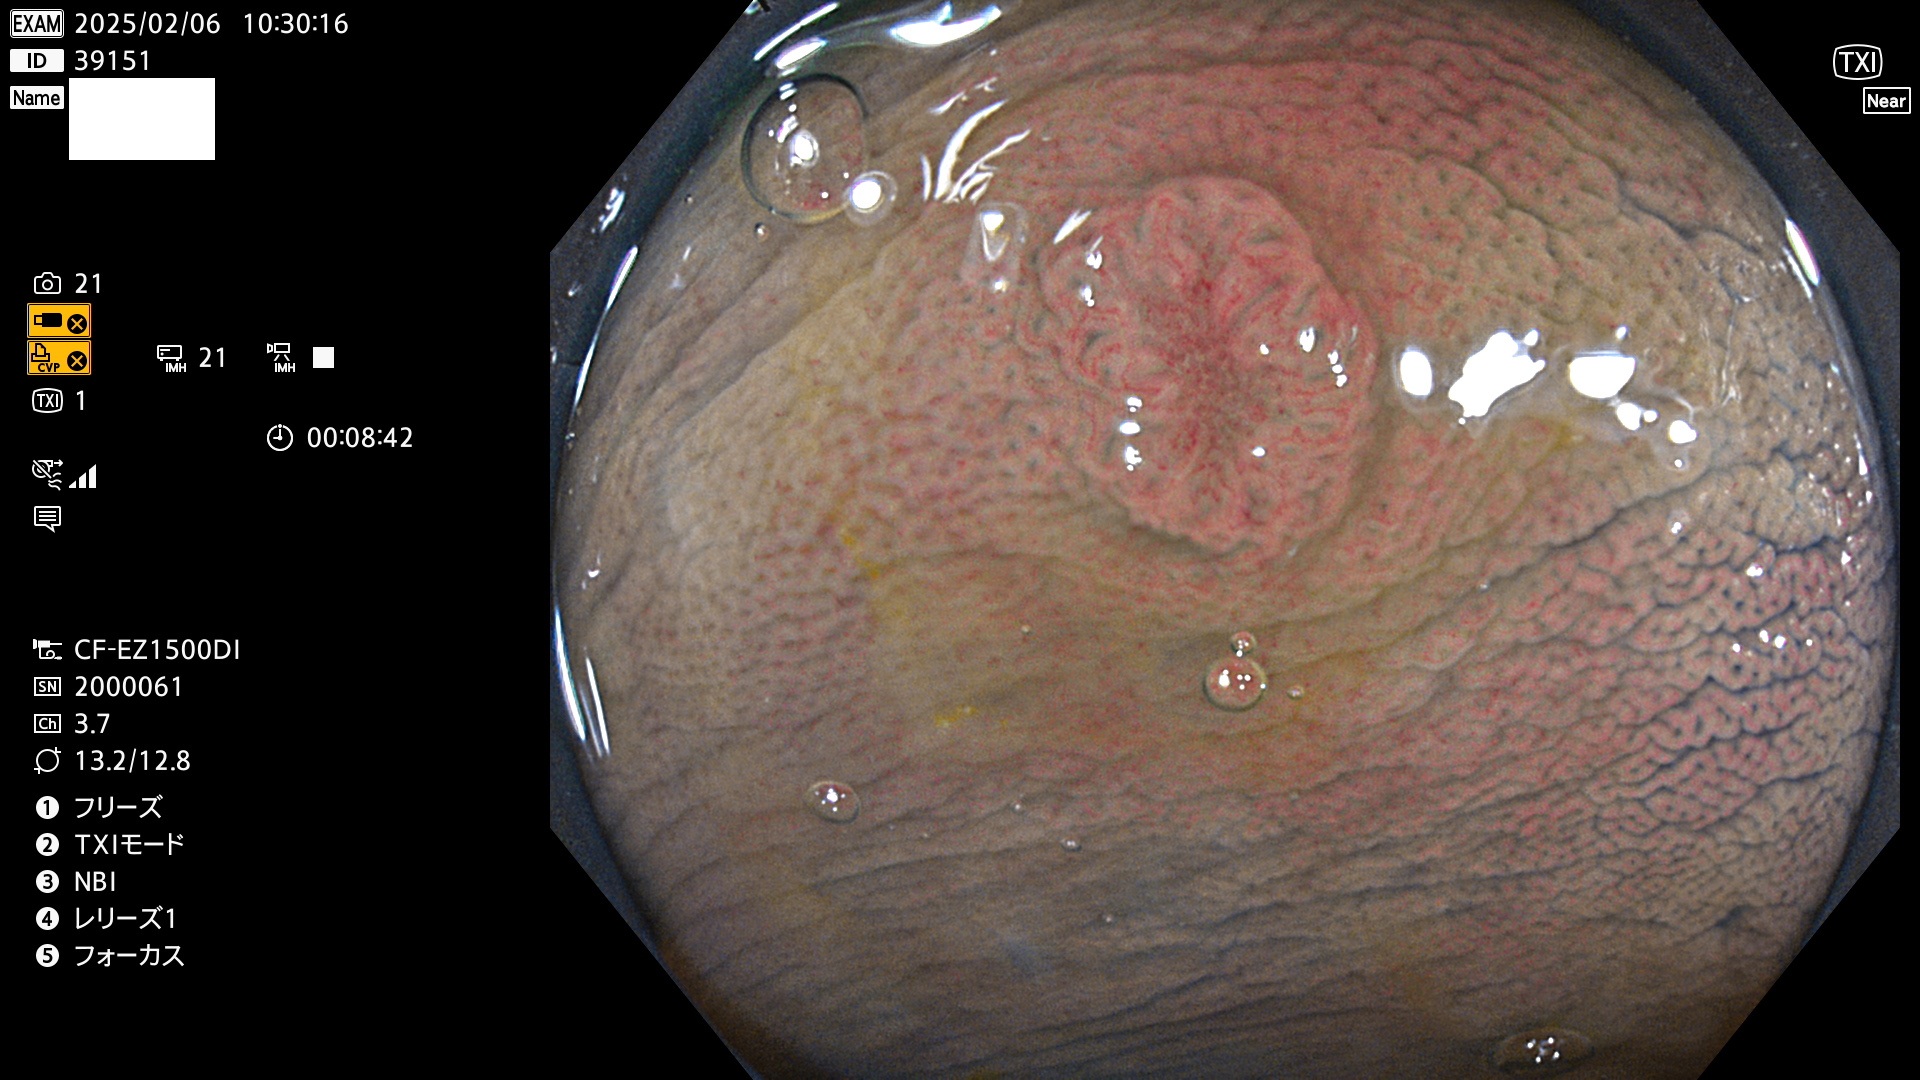

今週のUb、Uc型腺腫

完全に平坦な物をUb、陥凹している物をUcと呼びます。最も発見が難しく危険な病変です。

毎週の検査(木・金・土・日)に発見されたUb、Uc型・腺腫を、その週の日曜の夜にUPし1週間、提示します。

抽出の対象期間 2025年2月6日〜2月9日の4日間(48件の検査)7個 (7/48=14%)